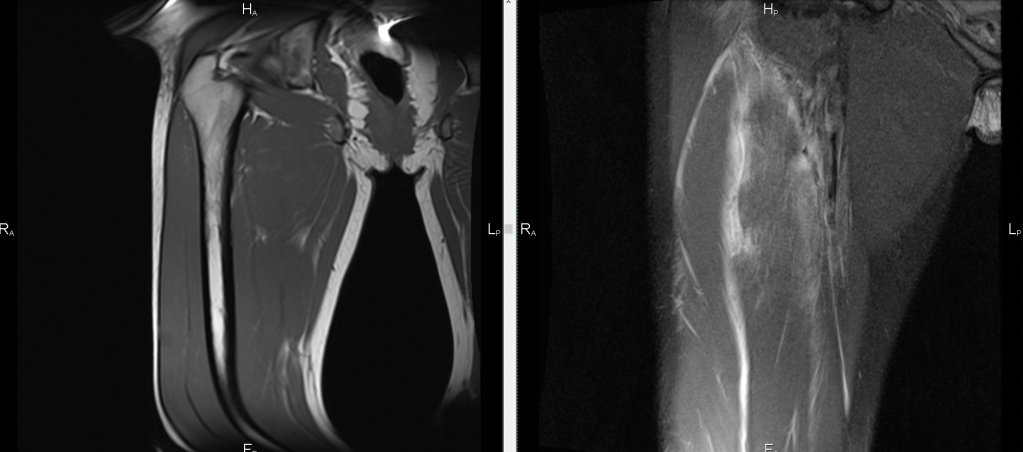

- МРТ – в обследовании примут участие и тазобедренный сустав и весь позвоночный столб. Такой способ также позволяет выявить состояние мягких тканей.

- МРТ. Обследуются последние отделы позвоночного столба, тазобедренный сустав. Способ дает возможность оценить состояние мягких тканей.